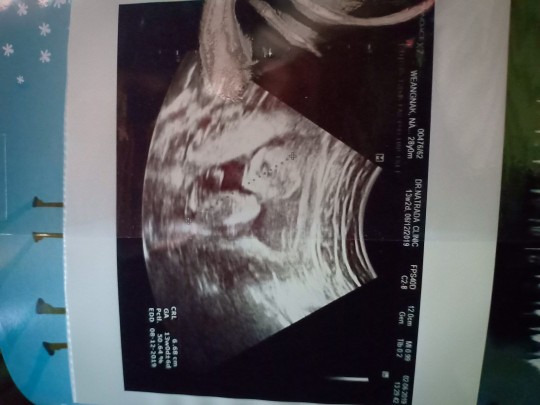

14W ค่ะ น้องนอนคว่ำ